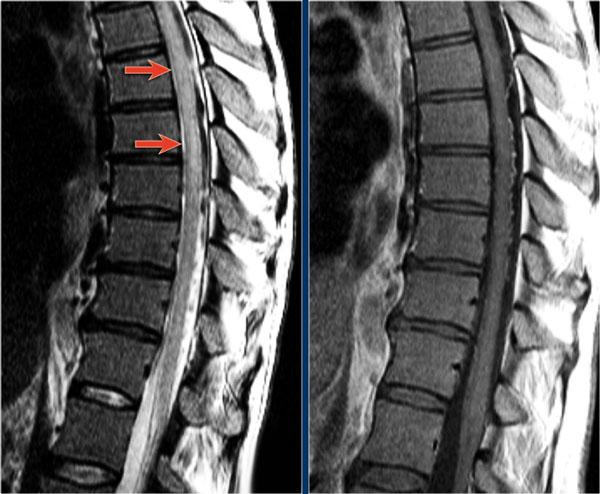

Đây là hình ảnh của một trường hợp TM điển hình.

Có tăng tín hiệu đa đoạn trên STIR và chuỗi xung T2W kèm theo phù nề nhẹ.

Phần lớn tủy sống trên đường kính ngang bị tổn thương.

Không có ngấm thuốc tương phản từ, đây thường là đặc điểm thường gặp trong TM.

Đôi khi có thể thấy ngấm thuốc dạng vá không đều.

Khi có ngấm thuốc tương phản từ, việc phân biệt TM với u tế bào hình sao (astrocytoma) có thể rất khó khăn.

Bên trái là hình ảnh của bệnh nhân nam 60 tuổi mắc u tế bào hình sao.

Bệnh nhân nhập viện với đau vùng ngực và rối loạn cảm giác chi dưới trái, tiếp theo là liệt nửa người trái.

Có tăng tín hiệu đa đoạn trên chuỗi xung T2W kèm phù nề nhẹ, tương tự như hình ảnh đã thấy trong các trường hợp TM.

Trên CE-T1W có vùng ngấm thuốc tương phản từ.

Vùng ngấm thuốc có hình thái nghiêng về u hơn, nhưng việc phân biệt vẫn còn khó khăn.